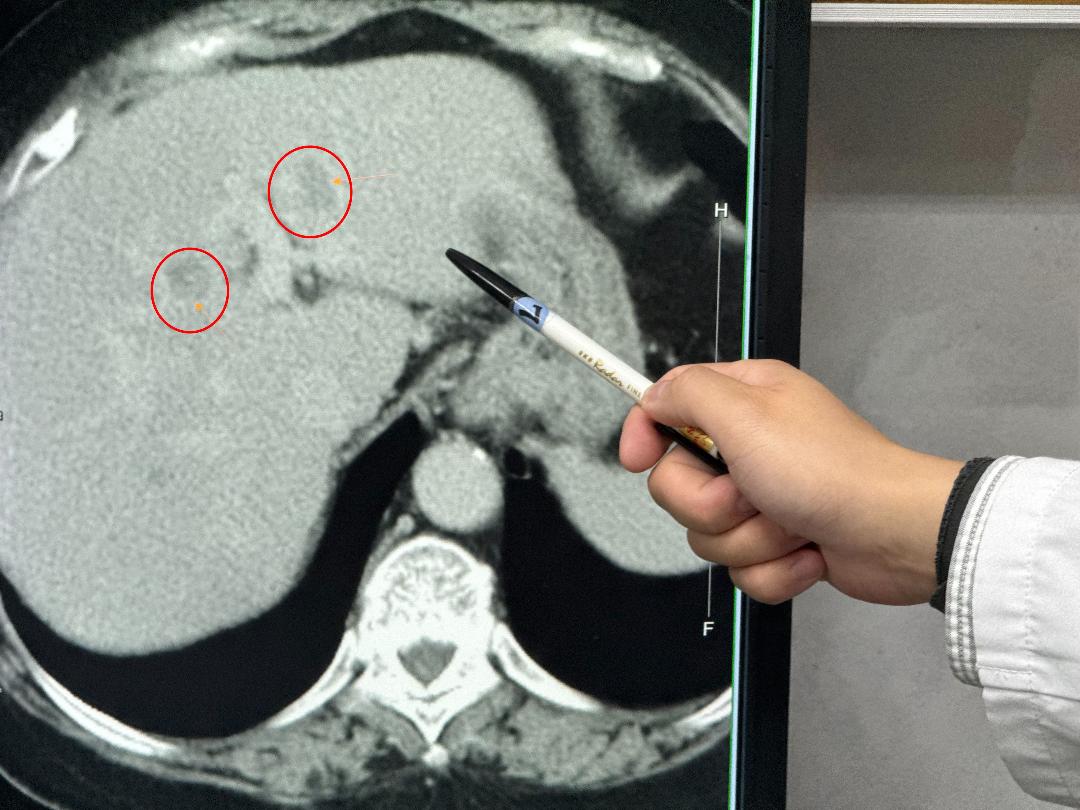

駐診在李綜合醫院的臺中榮總一般外科醫師吳坤達表示,婦人在門診腸胃科做超音波時發現有重度脂肪肝及疑似腫瘤,進一步檢查確認在肝臟的左外側葉及左葉中部各有一顆腫瘤,擔心把患者左邊肝臟全切除後,患者肝臟功能恐無法運作,因此,使用「類機械手臂」多關節器械系統切除左外側肝葉,及術中射頻消融治療術消除腫瘤。